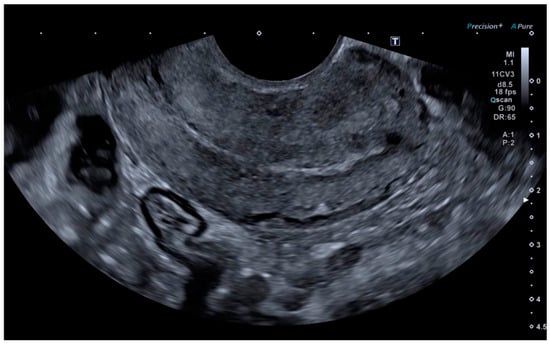

Ultrasonography showed an endometrial cavity occupied by a protruding formation in the uterine cavity measuring 38 × 15 mm, compatible with a uterine AVM (Figure 1). The presence of vascularisation of the right lateral uterine wall was noted, and pulsed Doppler showed a peak systolic velocity > 100 cm/s (Figure 2).

Figure 2. Colour and pulsed Doppler studies of the uterine arteriovenous malformation.